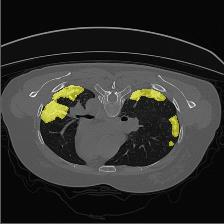

Medical image segmentation is one of the most fundamental tasks concerning medical information analysis. Various solutions have been proposed so far, including many deep learning-based techniques, such as U-Net, FC-DenseNet, etc. However, high-precision medical image segmentation remains a highly challenging task due to the existence of inherent magnification and distortion in medical images as well as the presence of lesions with similar density to normal tissues. In this paper, we propose TFCNs (Transformers for Fully Convolutional denseNets) to tackle the problem by introducing ResLinear-Transformer (RL-Transformer) and Convolutional Linear Attention Block (CLAB) to FC-DenseNet. TFCNs is not only able to utilize more latent information from the CT images for feature extraction, but also can capture and disseminate semantic features and filter non-semantic features more effectively through the CLAB module. Our experimental results show that TFCNs can achieve state-of-the-art performance with dice scores of 83.72\% on the Synapse dataset. In addition, we evaluate the robustness of TFCNs for lesion area effects on the COVID-19 public datasets. The Python code will be made publicly available on https://github.com/HUANGLIZI/TFCNs.

翻译:医学图像分解是医学信息分析的最根本任务之一,到目前为止已经提出了各种解决办法,包括许多深层次的学习技术,如U-Net、FC-DenseNet等。 然而,高精度医学图像分解由于医疗图像中存在固有的放大和扭曲,以及存在与正常组织密度相似的损伤,因此仍是一项极具挑战性的任务。在本文件中,我们建议TFCN(全面革命稠密网络的传输者)通过向FC-DenseNet引进ResLear-Transerferent(R-Transerfor)和Culvacial线性关注区(CLAB)来解决这一问题。TFCN不仅能够利用CT图像中更多的潜在信息来提取特征,而且还能够通过CLAB模块更有效地捕捉和传播语性特征和过滤非神经性特征。我们的实验结果表明,TFCN可以在Syapseion/SymblyDDS上以83CN-72 ⁇ 的分数实现状态。此外,我们在Synapse-DRIS数据设置上,我们还将评估CUTFTFI/LIS的可靠度。